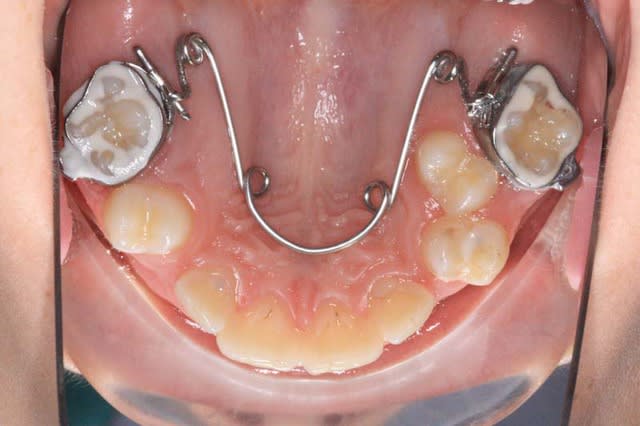

On ne peut pas toujours mettre un Q.H. classique dès le début du traitement, voici un exemple de Q.H. amputé de ses bras, qui sera sans doute poursuivi avec des Bk.

@+ Bjc.